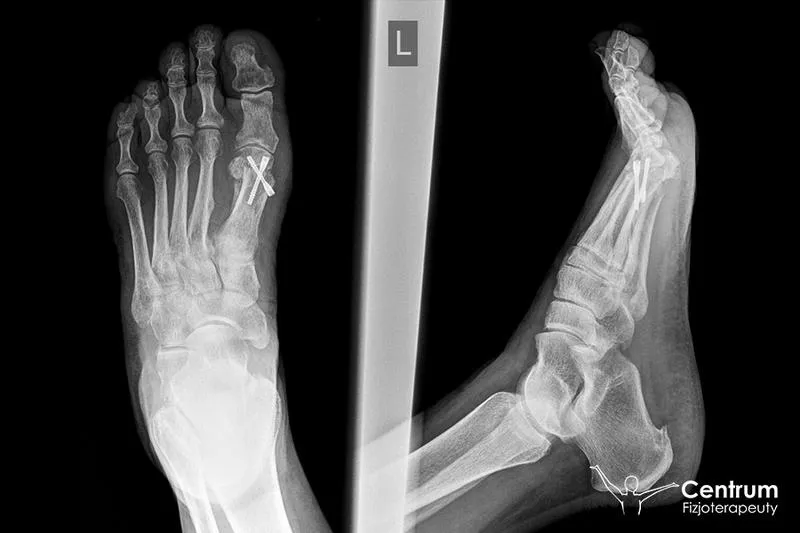

Rehabilitacja po urazie łąkotki to temat, który wzbudza wiele emocji. Każda osoba doświadczająca bólu stawu kolanowego z pewn...